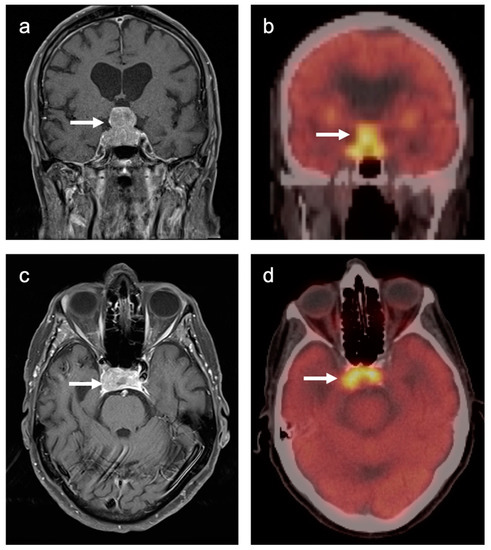

3.4. CNS Lymphoma

3.5. Brain Metastases

3.6. Response to Therapy